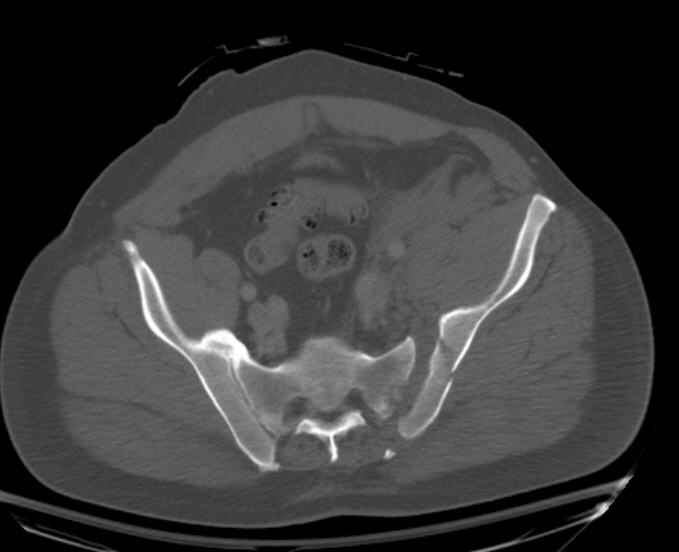

Hello gentlemen- Case is 52 YO male, fell out of treestand while deerhunting. He is 6 ft, approx. 260-275 lbs. Was hemodynamic unstable at local ER, sent to our Trauma center where circumferential pelvic binder placed and pt. stabilized with fluid, blood, and rewarming. Angiography not performed. An extraperitoneal bladder disruption was found, uro elected to treat non-operatively. Initial xray (not shown) demonstrated 5-7 cm wide at symphysis and SI joint. The first image attached is of CT once binder is in place. On post trauma day 5 the pt was taken to OR for ORIF of his iliac wing fracture and SI dislocation. The swelling/3rd spacing of fluid in the area of symphysis was profound, but quite acceptable posteriorly. Patient was prone for procedure, as I thought too difficult to fix the wing in lateral position. Of course the repair of wing was easy, but reduction of SI very demanding. The Floro images document the residual lack of reduction. That was the closest I could get it using 6mm joystick in wing, and clamp on sacrum and clamp through notch. The fixation was (initially) rigid. Anterior ex fix with supra-acetabular pins was placed due to condition of soft tissues, massive "beer-belly" overhanging the crest. Post trauma day ten patient's xray shows failure of posterior construct. Plan was to perform revision orif once soft tissues resolve considerably for full anrterior fixation and posterior fixation. However, while Im away for holiday (on Post trauma day 15), pt is developing septic clinical appearance, and trauma suspects pelvic abcess near symphysis and performs I and D - finds nothing but no primary closure performed. Posterior tissues/incision continue to look healthy. Now is post trauma day 17, pt is still tubed/on dopamine/and wbc still elevated, anterior incision still packed open. Clearly must get to bottom of possible sepsis, but then what? Thanks for you time - sorry for such lengthy clinical description. Thomas Schaller Kalamazoo, Michigan

My plan to revise fixation is in line with your suggestion - plate symphysis and anterior approach to SI joint. It appears from post - failure CT scan that the path of the more cephalad IS screw may be helpful to place a longer screw to engage opposite illiac wing as an option, or just anterior SI plates. not likely to do this tomorrow as he remains in a fragile clinical situation regarding his pulmonary status, and profound edema/induration around his pelvis/abdomen and thighs.